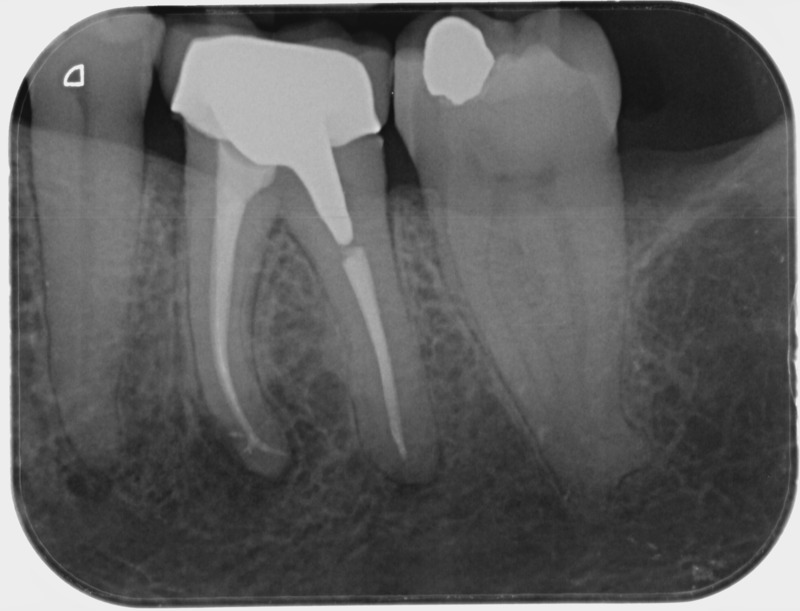

• Reprise de traitement endodontique : La manœuvre consiste à retourner à l’intérieur des racines d’une dent déjà traitée. Il arrive occasionnellement qu’une nouvelle inflammation se déclare suite à une reprise de carie ou une fracture de la dent, ou si le premier traitement endodontique est incomplet. Après s’être assuré que la dent lésée était conservable, il convient de désinfecter de nouveau le réseau canalaire parfois très complexe. La nouvelle obturation des canaux devra être protégée aussi rapidement que possible pour éviter une éventuelle contamination bactérienne.

Avant